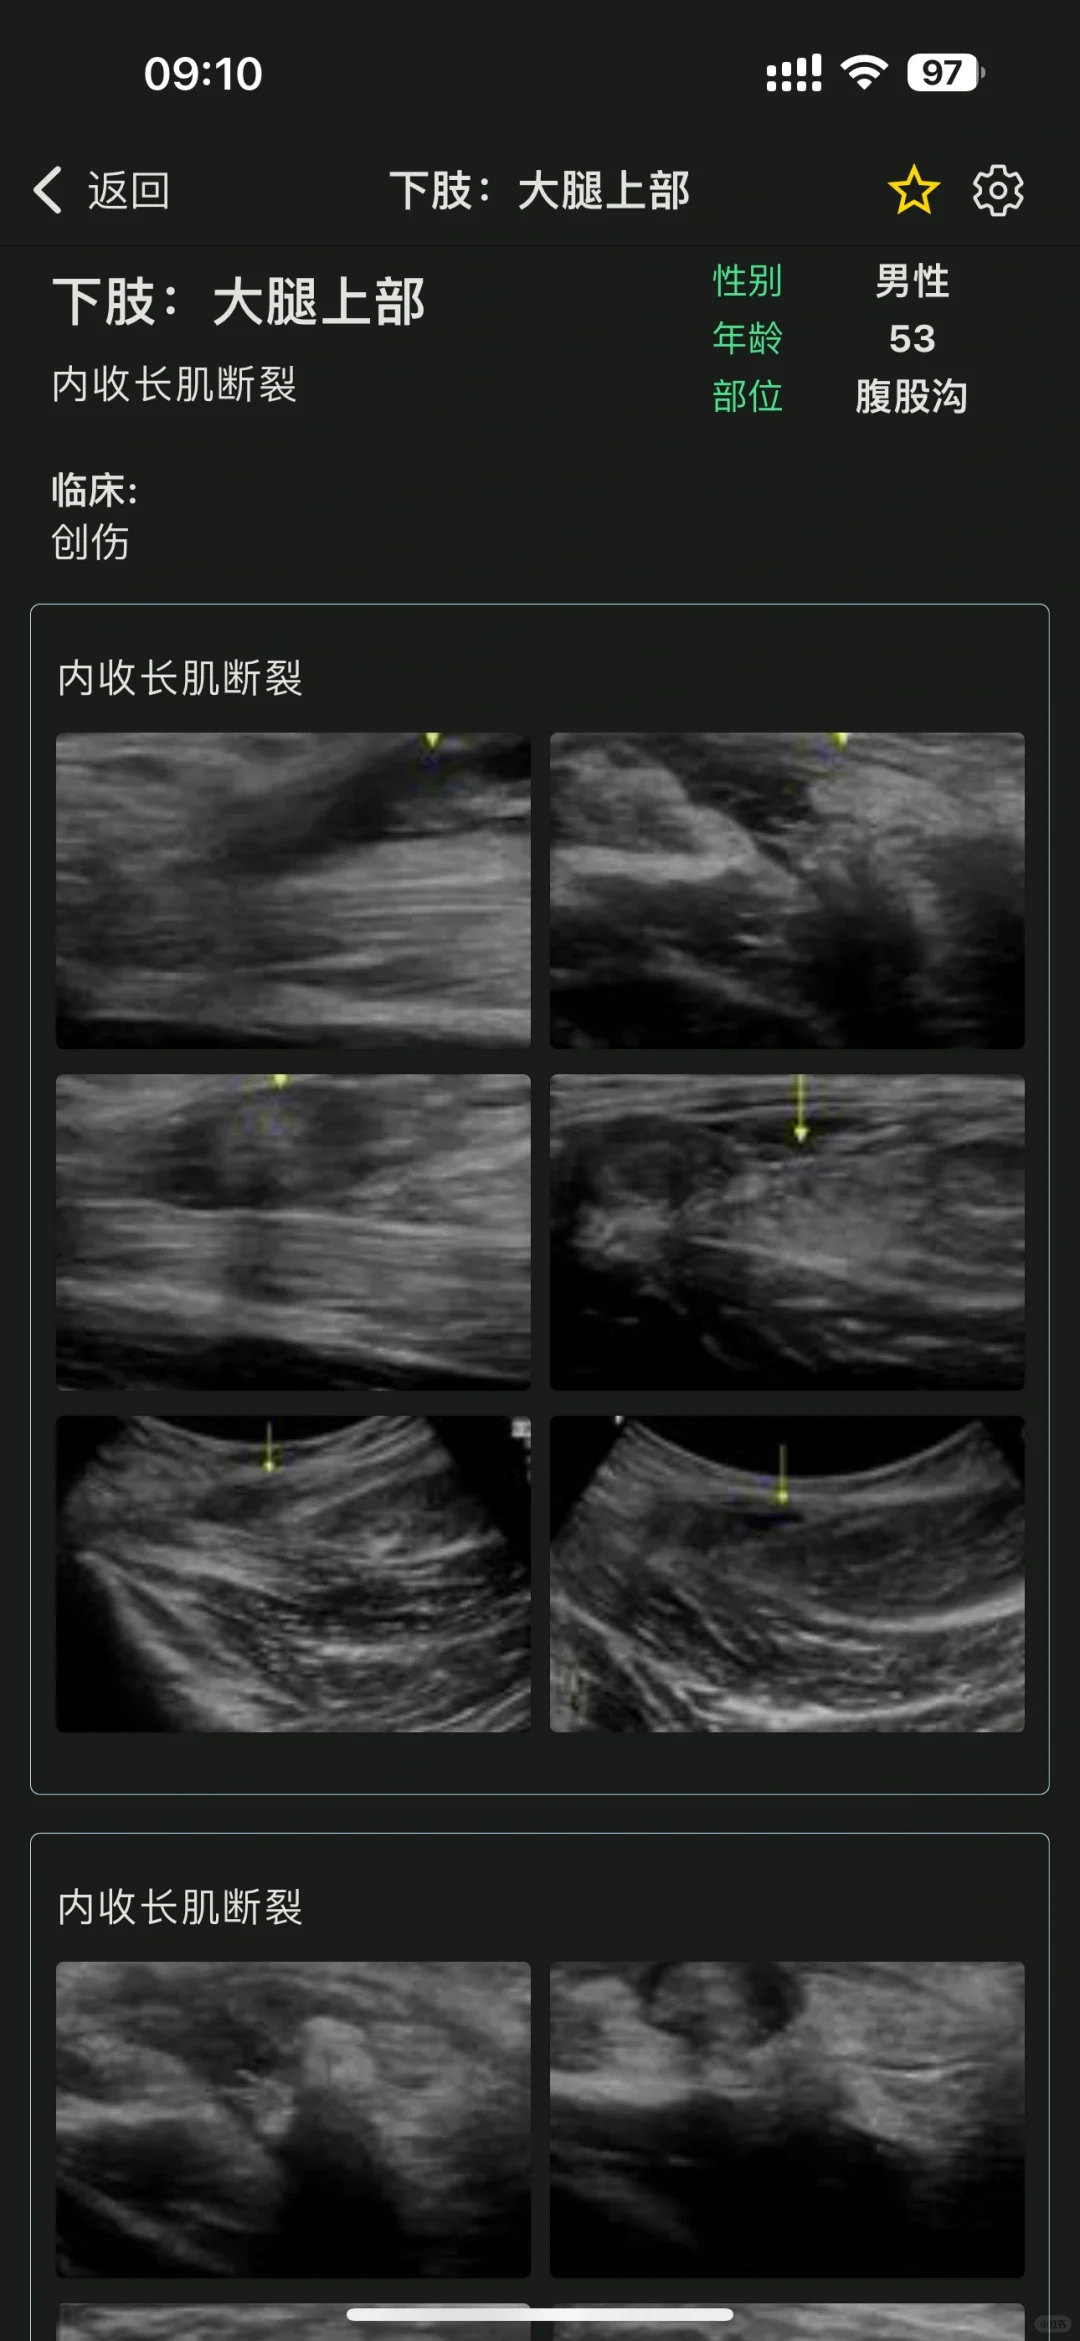

这个app简直就是超声界的“百科全书”。里面有数万个临床真实病例,数万张超声图像,每一个病例都有详细的分析和解读。不管是刚入门的小白,还是经验丰富的超声医生,都能在这里找到实用的知识。比如,我在做腹部超声检查时,遇到一个不太确定的病例,打开app一查,立刻就有了思路,太实用了!